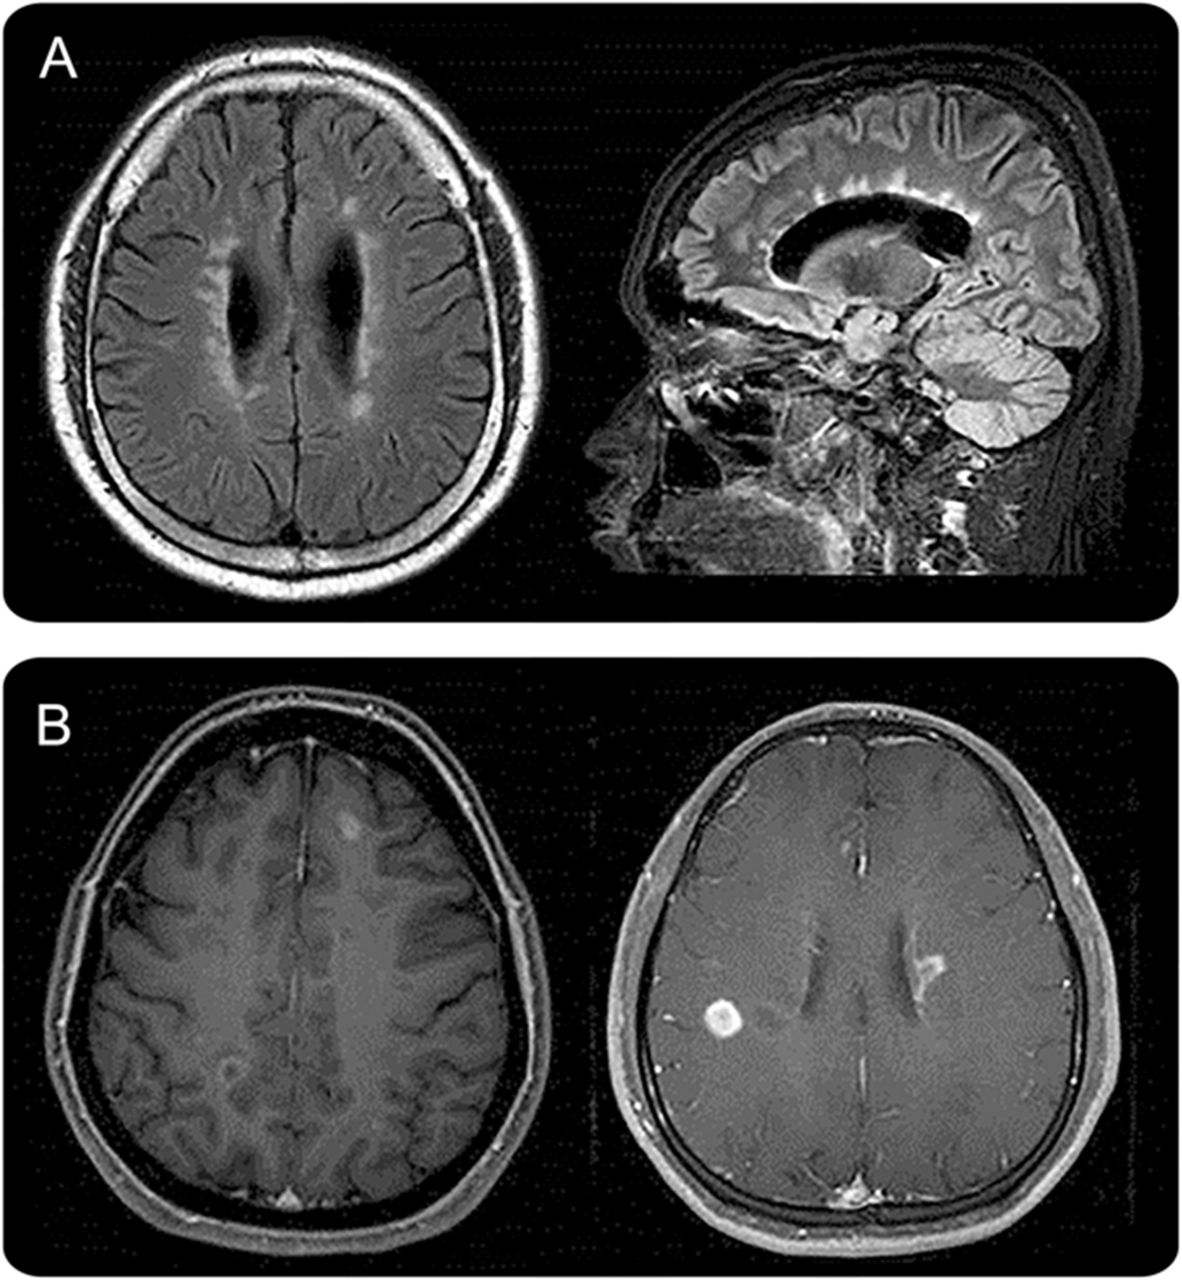

间脑的第三脑室和脑导水管周围病变。

间脑的第三脑室和脑导水管周围的病变,包括丘脑、下丘脑、中脑的前边缘在NMOSD已报告(图1一个)。10,12这些病变通常无症状,但有些病人可能有抗利尿激素分泌不当综合征,e6嗜睡症,e7体温降低,低血压,嗜睡,肥胖,e8甲状腺功能减退、高泌乳素血症、继发性闭经、乳溢和行为变化。e9

间脑的病变周围(一)第三脑室和脑导水管,(A.b),包括丘脑、下丘脑、中脑的前边缘(交流)。(本科)背脑干损伤邻近第四脑室,(反方向)线性髓病变与颈脊髓损伤,相邻(公元前)水肿和大量的背侧脑干病变涉及小脑脚。(一个)立即胼胝体病变侧脑室,室管膜衬后,(C.b)“大理石模式”胼胝体的病变,(运费到付)“拱桥模式”胼胝体的病变。块状半球白质病变,簇状(地方检察官)(D.b)长spindle-like或放射状病变白质束后,(特区)广泛和汇合的半球病变显示表观扩散系数地图上增加扩散系数表明vasogenic水肿,(d)在慢性阶段半球病变显示cystic-like腔的变化。(E.a)皮质脊髓束损伤涉及的内囊后肢和中脑(后代e.b.)大脑脚(欧共体)纵向锥体束后广泛的病变。(范围内)的云雾状增强(F.b)侧脑室的室管膜表面的线性增强,(F.c)脑膜增强。

背侧脑干病变毗邻第四脑室。

最具体的脑部MRI异常患者NMOSD是背脑干病变毗邻第四脑室包括postrema面积和细胞核大港solitarius。这种病变是高度与顽固性呃逆,恶心、呕吐,10,12,21和在7%到46%的已报告NMOSD患者。12,15e1, e10汽油这个区域,催吐的反射中枢,没有那么严格的血脑屏障,使它更容易AQP4-IgG攻击。核磁共振以及临床证据支持这一概念,区域postrema NMOSD患者是一个重要的点的攻击,进一步表明,这一地区是一个门户循环免疫球蛋白进入中枢神经系统。22,23病理异常被发现在这一地区40%的患者动,但没有明显的神经元,轴突或髓鞘的损失。21髓损伤与颈脊髓损伤通常是连续的,通常采取线性形状(图1反方向)。这些病变可能与疾病的最初症状22,24或预示急性恶化。25各种脑干病变可能出现相应症状,如眼球震颤、构音障碍、吞咽困难、共济失调、眼肌麻痹。15,20.、e11 e12汽油

Periependymal侧脑室周围的病变。

在胼胝体病变中描述NMOSD患者的12%到40%。12,15,26因为动校正和女士经常有胼胝体的病变,本身并不是一个独特的位置发现NMOSD有别于然而女士,女士的胼胝体的病变是离散的,卵形的,垂直于心室和涉及胼胝体的低等方面(图2一个),e13, e14灯头NMOSD病变位于侧脑室立即旁边,后室管膜衬(图1一个)。12急性胼胝体的病变NMOSD经常水肿和异构,创建一个“大理石的模式”26有时涉及完整的厚度压部在一个独特的“拱桥模式”(图1中,C。b和运费到付)。12有时,大脑半球的胼胝体病变延伸到,形成一个广泛和汇合的白质病变。12NMOSD在慢性阶段,胼胝体的病变往往规模和强度降低,甚至消失26;然而,囊性变化,描述了胼胝体萎缩。e15某些临床症状,如认知和运动协调障碍,可能归因于胼胝体的病变,但他们还没有被很好地评估。

半球的白质病变。

广泛和汇合的半球的白质病变是块状(> 3厘米直径最长)簇状经常或长期以来spindle-like放射状白质束(图1 d)。12质量效应通常是缺席的。e16天病灶扩散系数增加表观扩散系数地图上表明vasogenic水肿与急性炎症(图1特区),12,27偶尔模仿后部可逆性脑病综合症28或Balo病变。e17, e18发现了这些广泛病变更频繁地在anti-AQP4抗体血清反应阳性的血清反应阴性的病人。29日在慢性阶段,这些大病变倾向于缩小甚至消失,但是在某些情况下,cystic-like或空洞的变化显示(图1所示的代码)。e19, e20这些病变可能导致各种症状如轻偏瘫、脑病、视野缺陷取决于它们涉及的面积。大汇合的半球的白质病变与NMOSD孩子并不罕见。Tumefactive病灶周围水肿带和变量质量效应可能类似于急性播散性脑脊髓炎20.,30.或中枢神经系统恶性肿瘤。31日

病变包括皮质脊髓束。

病变包括皮质脊髓束可以单边或双边、并可能延长从深在大脑半球白质内囊后肢的到达大脑总花梗中脑、脑桥(图1 e)。12这些病变是连续的,通常纵向广泛,锥体束后(图1欧共体)。皮质脊髓束损伤被发现在23%到44%在一些群NMOSD患者12、e2在其他军团,偶尔被报道。11,13这是感兴趣的,与circumventricular地区,皮质脊髓束不AQP4的地区是高度表达;尚不清楚为什么这些地区也经常参与NMOSD。